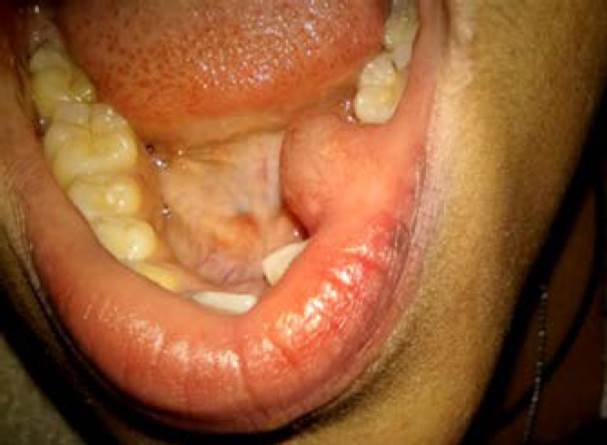

Durante el periodo evaluado (1997-2017), se recibieron y procesaron 14,186 muestras en el SAPyC del Hospital Pediátrico «Juan Pablo II», de los cuales 63 casos correspondieron a lesiones de las glándulas salivales. Cuarenta y siete tuvieron diagnóstico histopatológico de mucocele (Figuras 1 y 2), representando el 74.6% de las lesiones de glándulas salivales, siendo por lo tanto la patología más frecuente en la población estudiada (Tabla 1).

Figura 1 Imagen clínica de mucocele del labio inferior. Se observa lesión oral elevada de 2 cm de diámetro, localizada en el labio inferior, de coloración rosa pálido y zonas azuladas, de consistencia blanda, dolorosa a la palpación, de un año de evolución. Diagnóstico histopatológico correspon diente con mucocele.